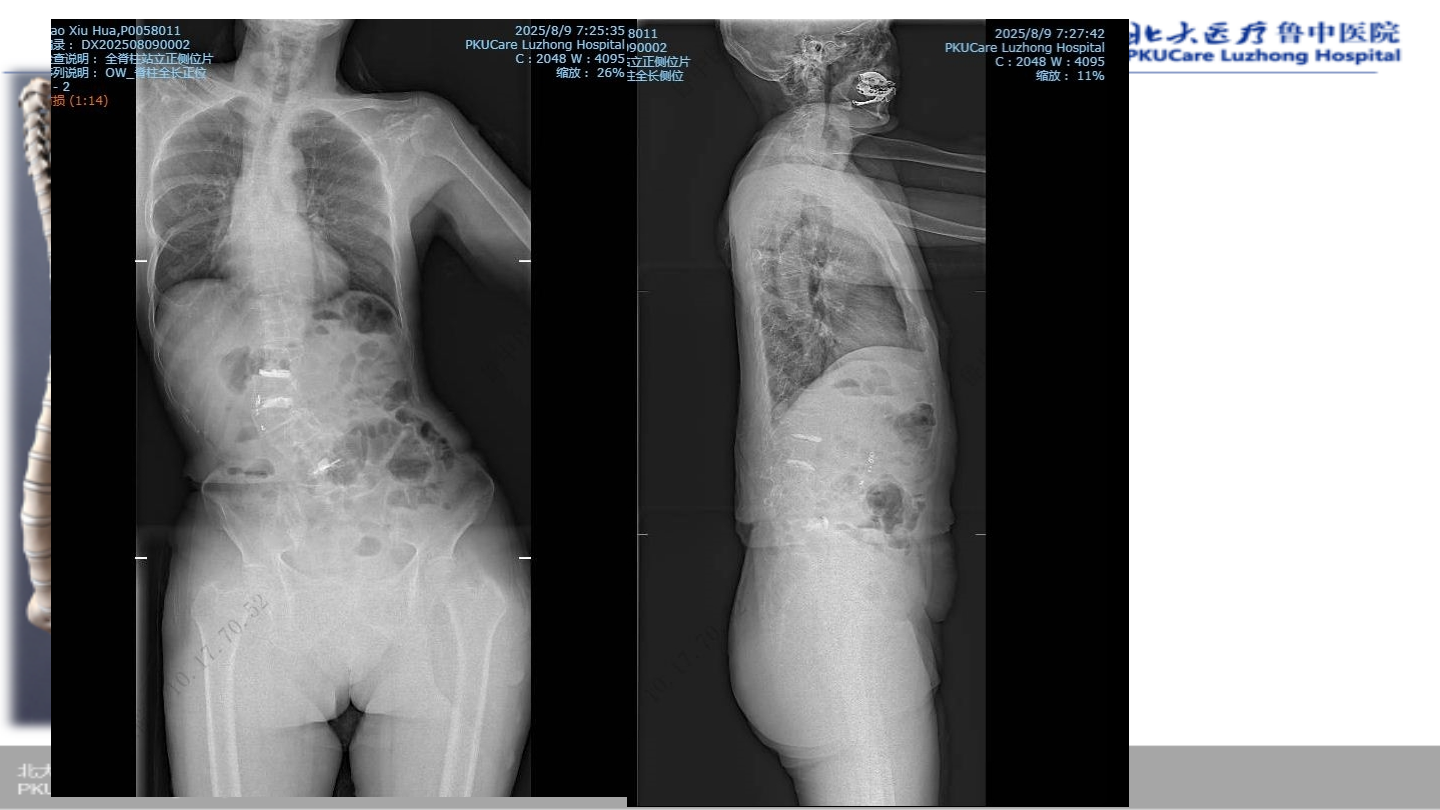

术后